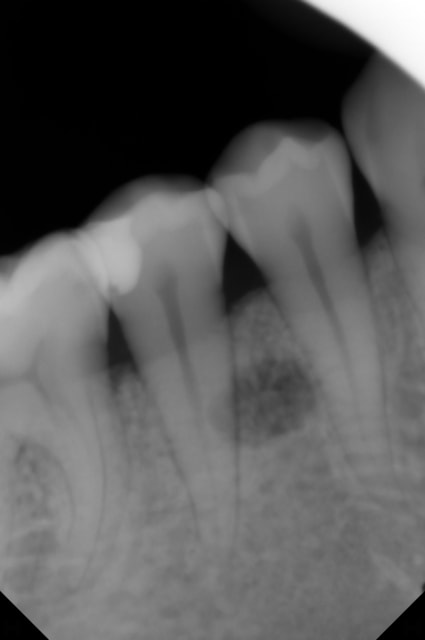

Une patiente 25 ans me décrit des douleurs relativement intenses au froid sur la 45. Je fais une rétro, je visualise la carie et une image radioclaire en regard de la 45.

J'ai fait plusieurs rétro avec des angulations différentes.

Serait-ce une lacune de Stafne ?

Je dirai d'après les rx que pas de rapport entre les dents et cette lacune. Ce n'est pas dans le même plan. Direction chir bu spécialisé et ana pat pour savoir précisément.

les douleurs au froid peuvent être liées au syndrome septum car on voit bien une atteinte radio à ce niveau.

l'image radio-claire peut être fortuite dans la mesure où elle ne semble pas du tout liée à 45 d'après tes différents clichés cette lésion serait davantage sur le versant lingual.

et pour la lacune de stafne non.